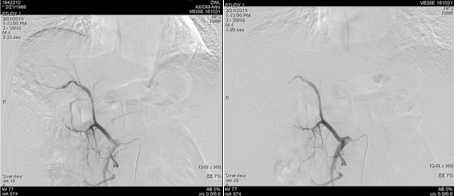

2019年1月17日(术后1个月)入院复查,影像学见疑似复发病灶。                         图片

图:影像学检查(2019-01-17)

遂予肝动脉化疗栓塞(TACE)治疗,行数字减影血管造影(DSA)可见肝右叶多个结节状肿瘤染色,明确肝左、右动脉分支为肿瘤供血动脉,判定为外科术后复发。

图片

图:第一次TACE治疗